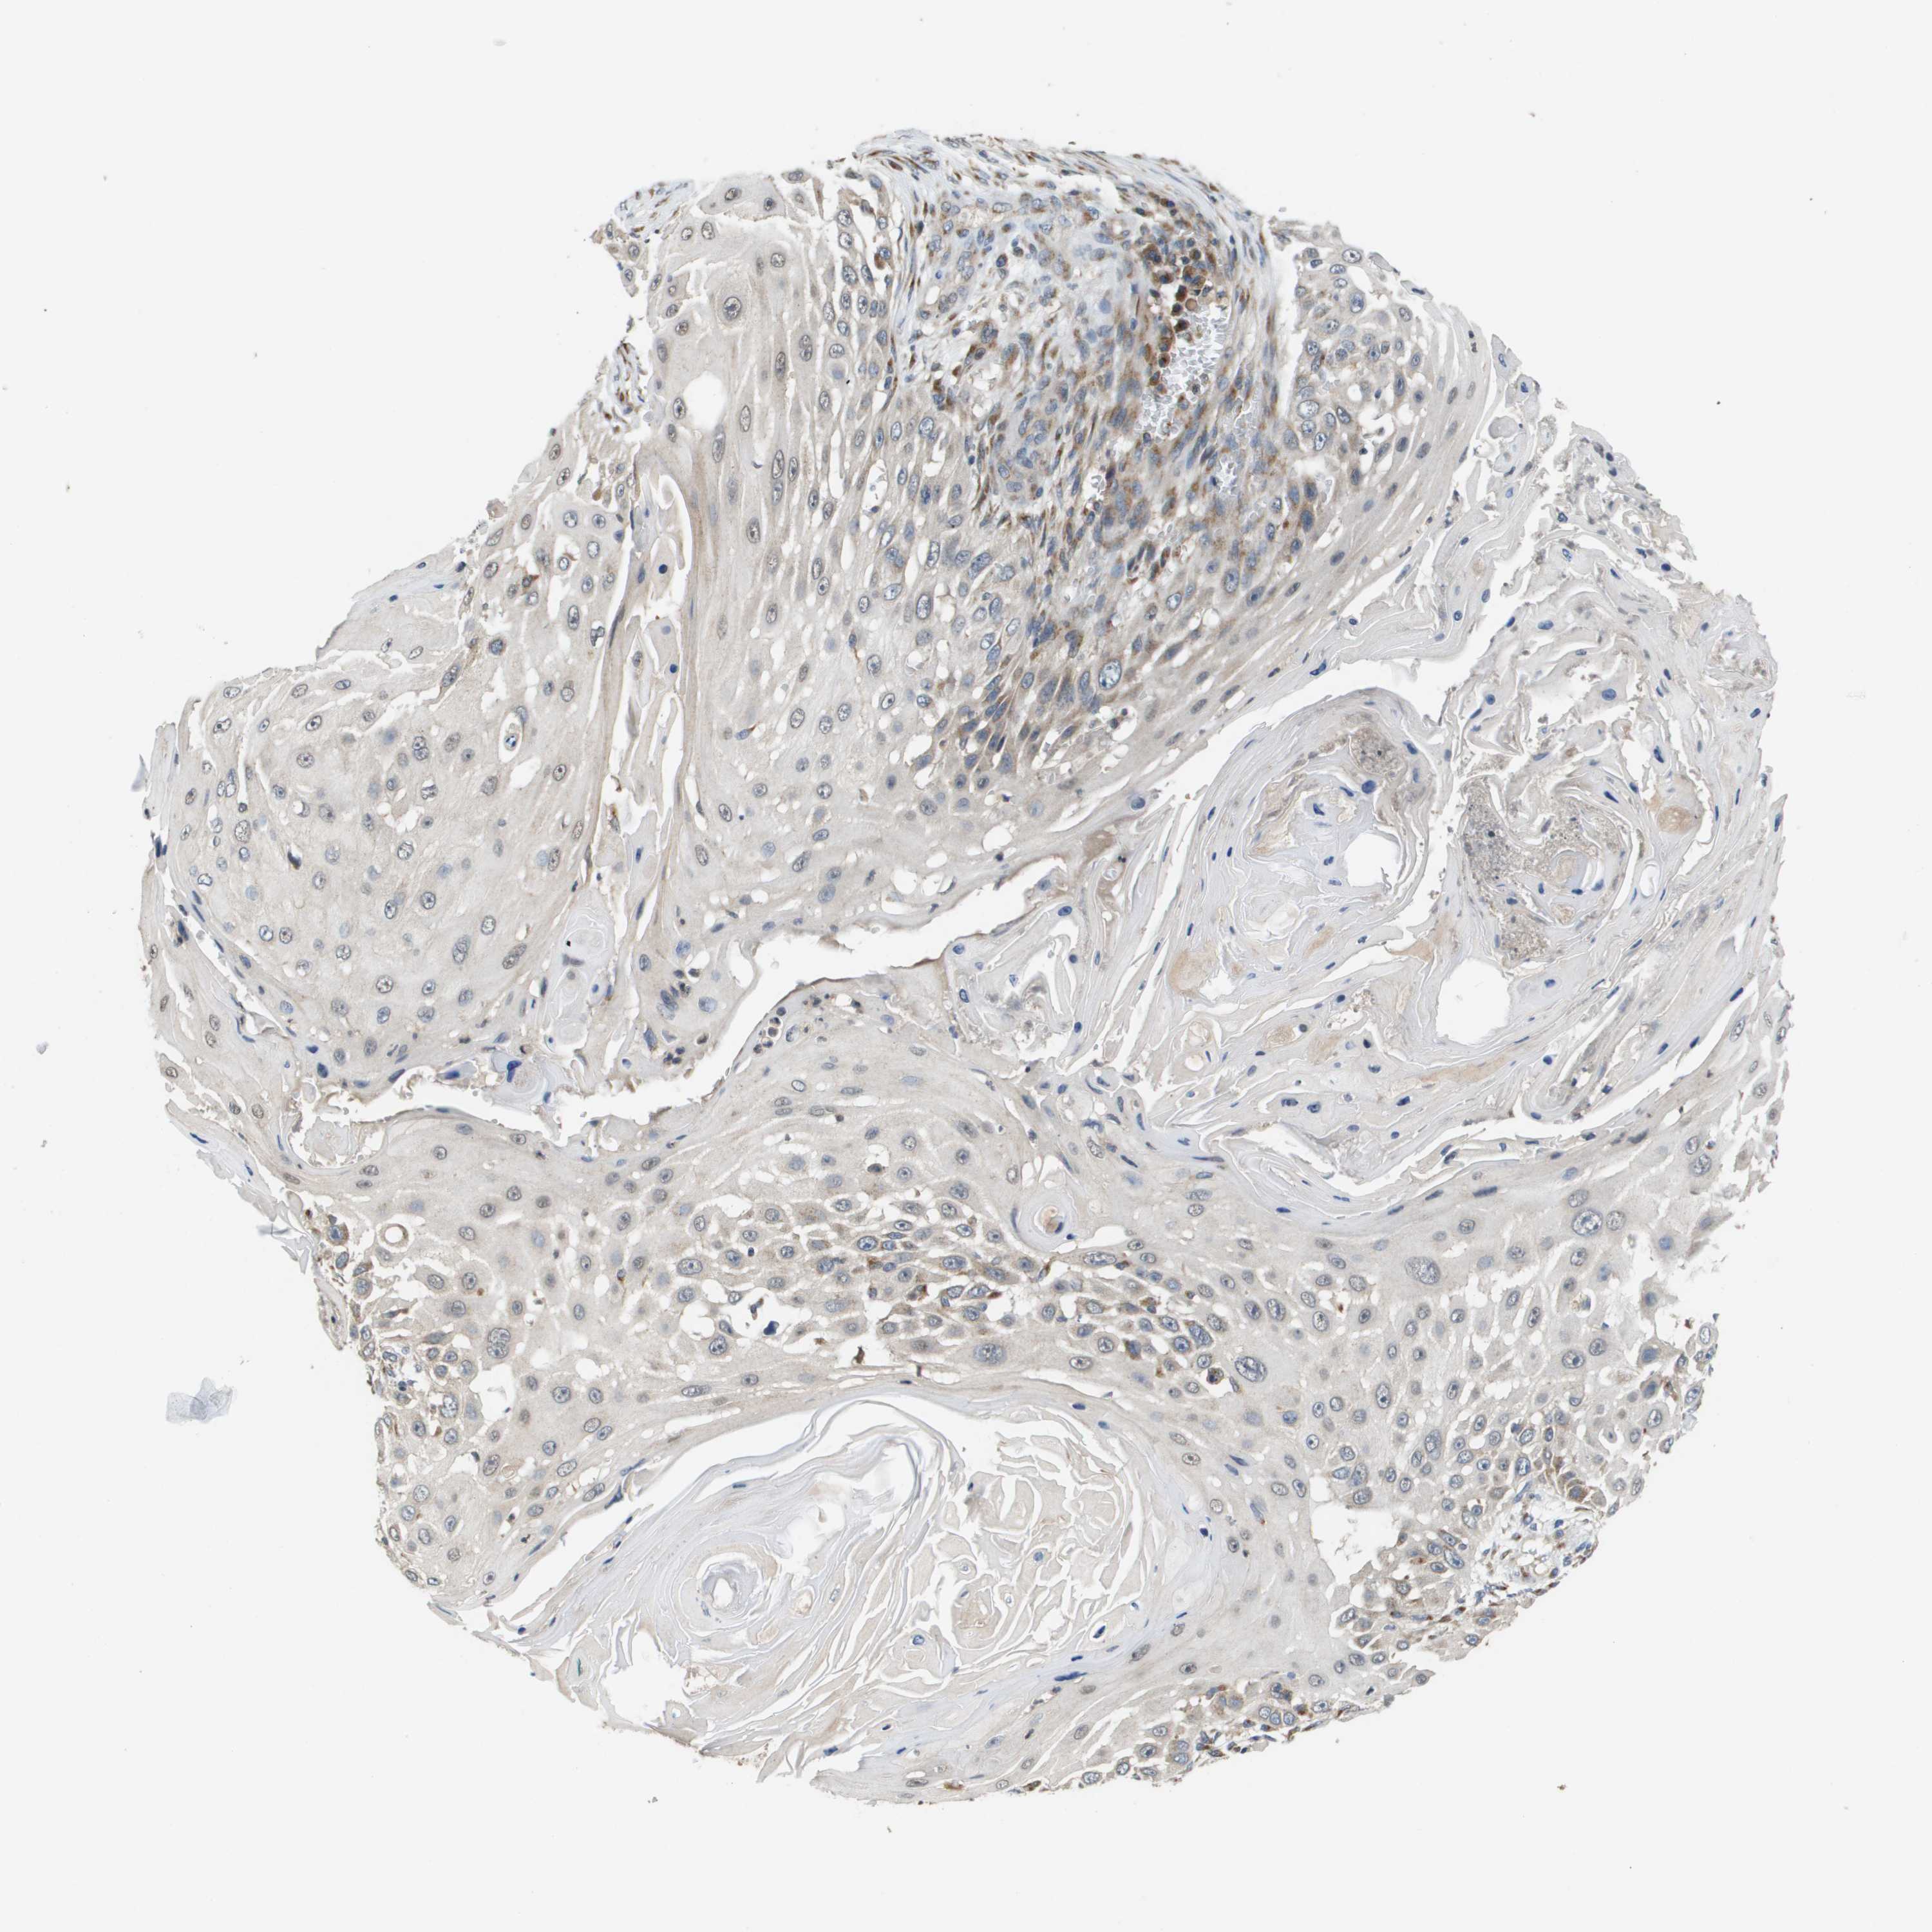

SKIN CANCER - Protein expressioni

A mouse-over function shows sample information and annotation data. Click on an image to view it in a full screen mode. Samples can be filtered based on level of antibody staining by selecting one or several of the following categories: high, medium, low and not detected. The assay and annotation is described here.

Antibody stainingi

Antibody staining in the annotated cell types in the current human tissue is reported as not detected, low, medium, or high, based on conventional immunohistochemistry profiling in selected tissues. This score is based on the combination of the staining intensity and fraction of stained cells.

Each image is clickable and will lead to virtual microscopy that enables deeper exploration of all samples and also displays staining intensity scores, fraction scores and subcellular localization as well as patient and tissue information for each sample.

Antibody HPA006277

Squamous cell carcinoma, NOS